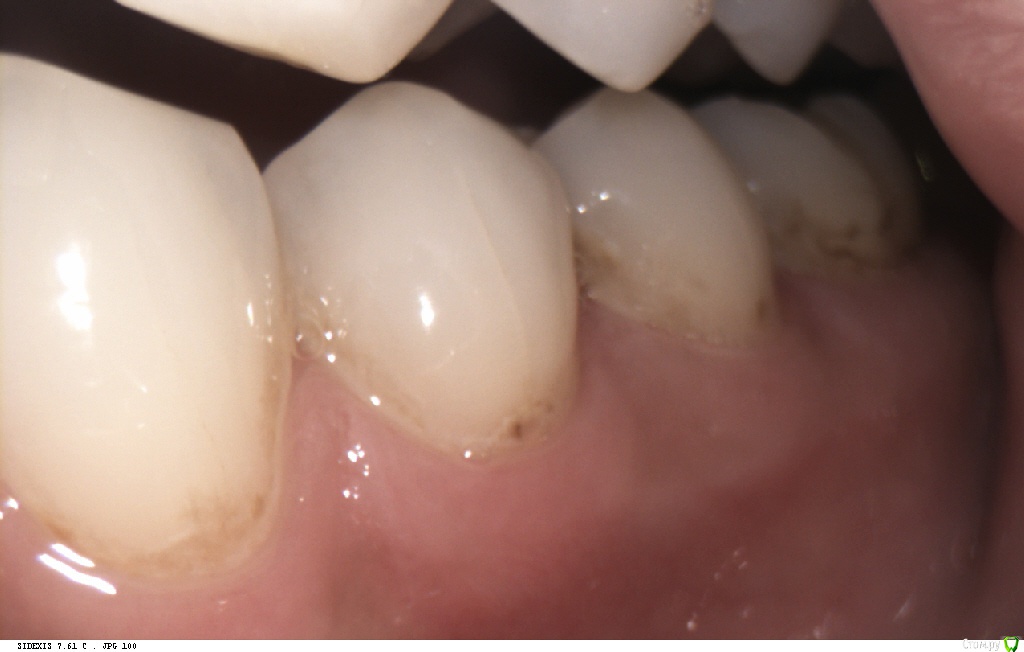

Pan Опубликовано 6 мая, 2017 Поделиться Опубликовано 6 мая, 2017 (изменено) типичная локализация кариеса при плохой гигиене и злоупотреблении в питании фастфуда. Ну понятно, что всё это на фоне сниженной кариесрезистентности. Первым делом нужно объяснить девушке значимую роль питания и гигиены в развитии кариозных процессов. Изменено 6 мая, 2017 пользователем Pan 1 Ссылка на комментарий

Л Ю С Я Опубликовано 9 мая, 2017 Поделиться Опубликовано 9 мая, 2017 Прям Фауст фуд во всем и виноват))) и гигиена по фото не такая уж плохая. Зубные отложения, конечно, присутствуют. Но гингивита, характерного для регулярно неудовлетворительной гигиены нет. У меня есть пациентка, тоже около 30, очень сознательная, со здоровьем и образом жизни все в порядке, регулярно использует флосс, щётка электрическая. Там кпу 26-28. Удаленных зубов нет, за счёт регулярного посещения стоматолога. Депульпированных 4-5. Ходила раз в 3 месяца , стабилизировали процесс за счёт профессиональной гигиены, антибактериальными ополаскивателями, туфмусс и фторированием. Исчезла на 1 год, случилась беременность и роды. Явилась через 2 месяца после родов. Гигиена отличная, Фауст фуд не ест)), зато кариес съел практически все целые контакты и шейки. Мотивируем на Тотал 1 Ссылка на комментарий

Pan Опубликовано 11 мая, 2017 Поделиться Опубликовано 11 мая, 2017 (изменено) Деструкция эмали (в типичных для зубного налета местах) произошла значительно ранее ( разве нужно еще раз говорить об истинных причинах, способствующих этому процессу?) Потом, конечно, индивидуум (взрослея) изо всех сил старается и отсутствие признаков гингивита(если хотите) тому подтверждение. Но, увы, процесс уже запущен... Вы конечно же не хотите оспорить тот факт, что деструкцию эмали (кариес) вызывают бактерии зубного налета. Изменено 11 мая, 2017 пользователем Pan Ссылка на комментарий